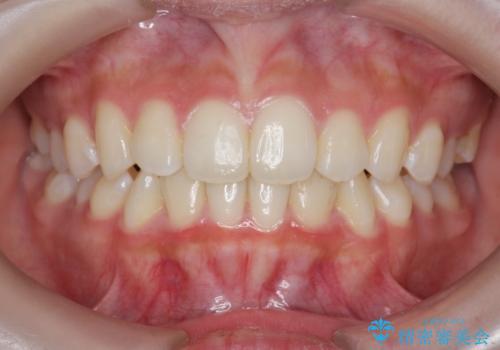

インビザラインライトで行う短期マウスピース矯正治療

- 前歯のガタつきを並べたいたいと、矯正治療を希望され来院されました。

とにかく短期間で前歯だけの治療を行いという希望が強く、全体矯正と前歯だけの部分矯正の仕上がりのイメージを確認したのち14枚のマウスピースで前歯のみの矯正治療を行っていくこととしました。

インビザラインライトは軽度なガタつきや傾斜の改善に用いられる全14枚のマウスピース矯正です。

短期間で治療の終了が見込めるだけでなく、料金もインビザラインフルに比べリーズナブルです。